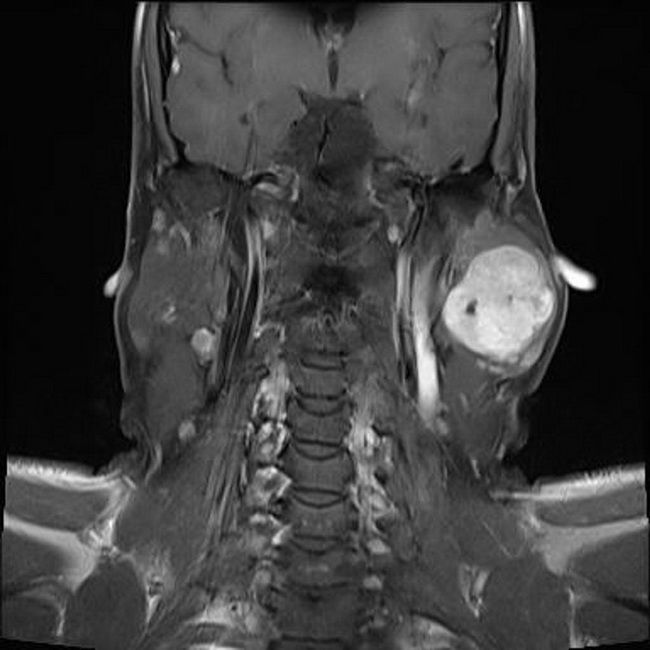

Атерома мрт

Атерома мрт 111 фото